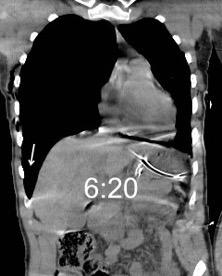

Marzo 2014: Perforación longitudinal distal secundaria a episodio de vómito (síndrome de Boerhaave). Derrame pleural izdo. que evoluciona a empiema.

Wang C-T et al. Tension hydropneumothorax in a Boerhaave syndrome patient: A case report . World J Emerg Med, 2021. Katabathina V et al. Nonvascular, nontraumatic mediastinal emergencies in adults:a comprehensive review of imaging findings. Radiographics. 2011.